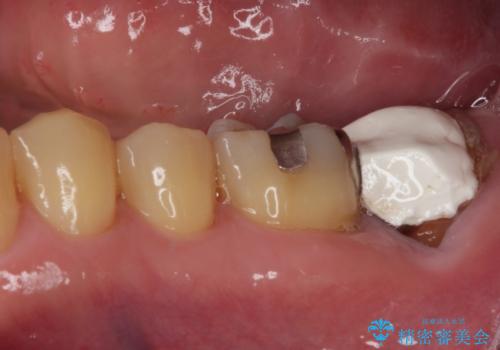

- 奥歯のむし歯治療を希望して来院された患者様です。

上顎の奥歯は、左右ともに外側に転位しており、特に右上はむし歯の範囲が広く、根管治療も必要な状態でした。

左下の奥歯は状態が非常に悪く、保存は困難と判断されたため、インプラントによる補綴治療が必要でした。

上顎左右の歯をアンカースクリューを用いた部分矯正により位置を修正し、オールセラミッククラウンにて補綴治療を行うこととしました。